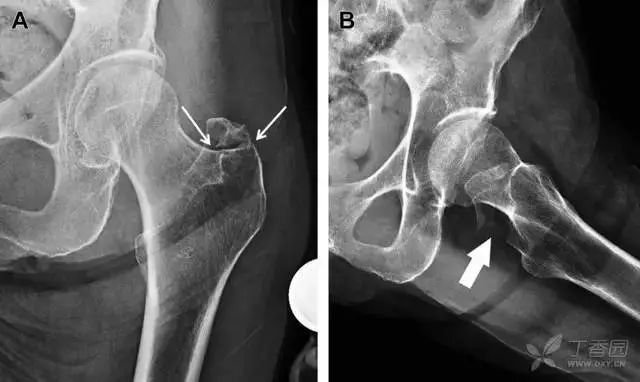

07非典型股骨骨折

另一种易漏诊的骨折是非典型股骨骨折,这种骨折与长期服用双膦酸盐相关,常发生在使用双膦酸盐 3 年以上的患者。前驱症状表现为腹股沟痛或大腿痛的患者中,60%~70% 被错误地认为由腰背痛或髋关节炎引起。

这种骨折的一个典型表现为火山口状骨膜隆起及一横行透亮带。值得注意的是,超过 50% 的患者表现为股骨干完全骨折。由于 50%~60% 的患者会累及双侧,所以一旦一侧下肢确诊,需行对侧下肢检查。

图 10 老年患者长期服用双磷酸盐引起的骨折。A 髋部正位片,箭头所示,股骨外侧皮质存在横行透亮带。B 后续的股骨 X 线片示局灶性骨膜反应,以及此类骨折的特征性表现-火山口状骨膜隆起(箭头)。C MRI 冠状位 STIR 序列扫描示相应骨折平面的骨髓水肿表现